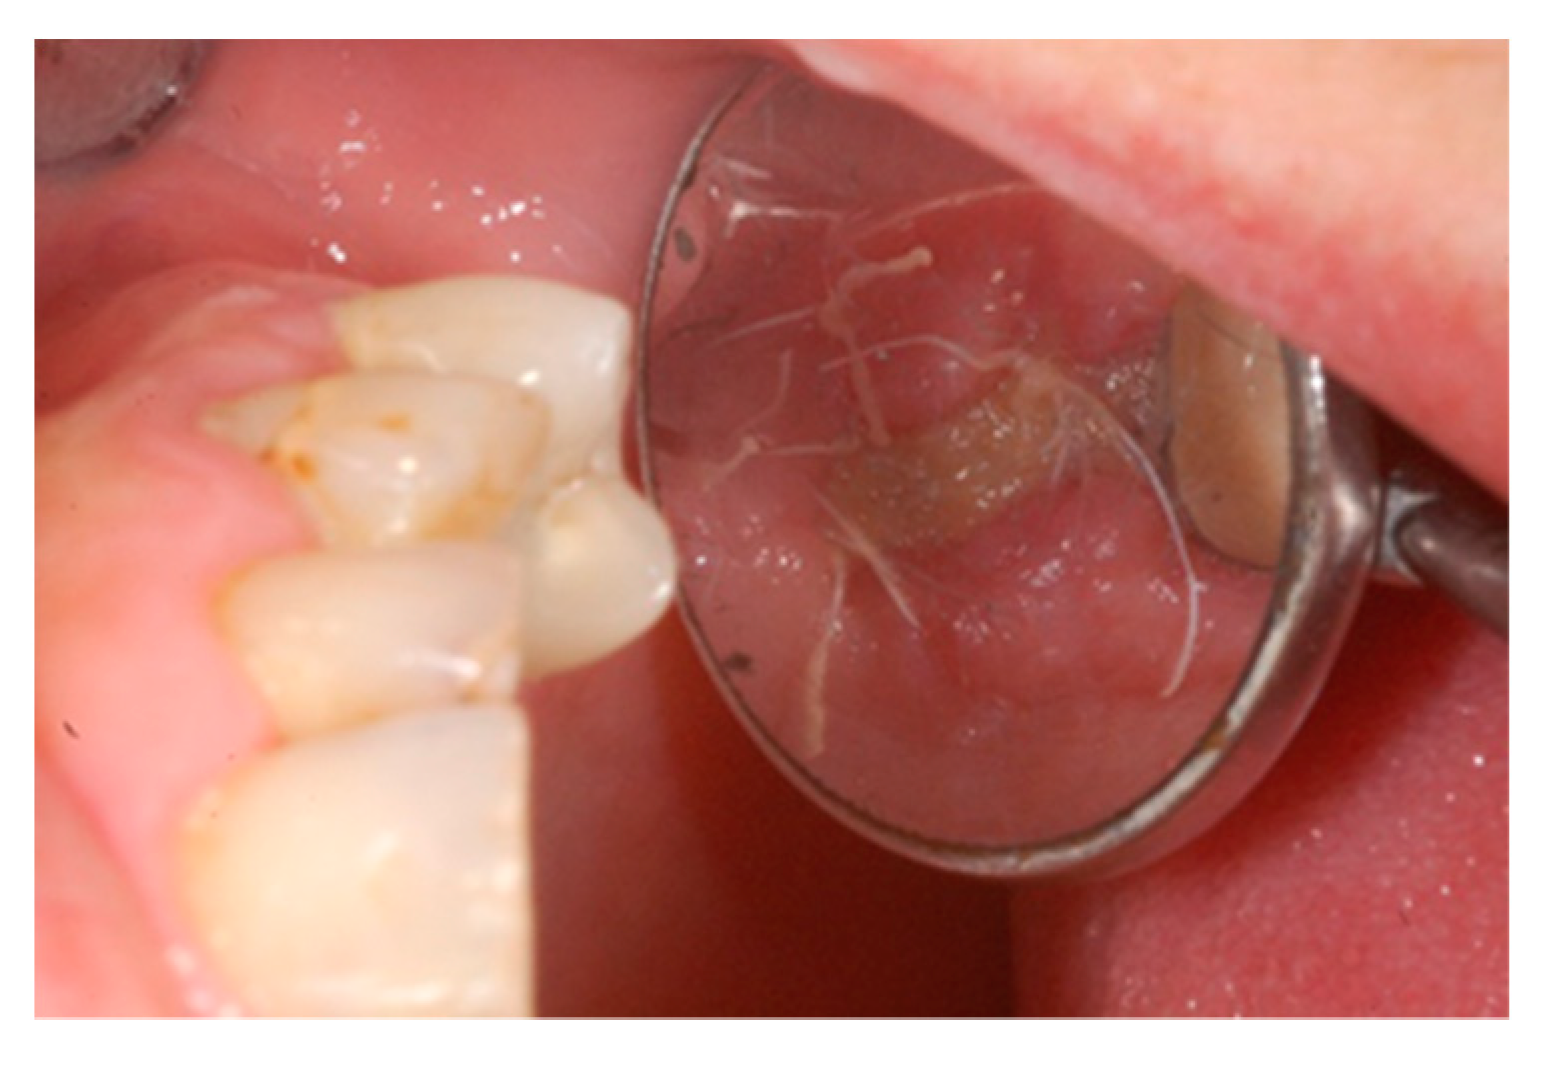

2. Case Report

3. Results